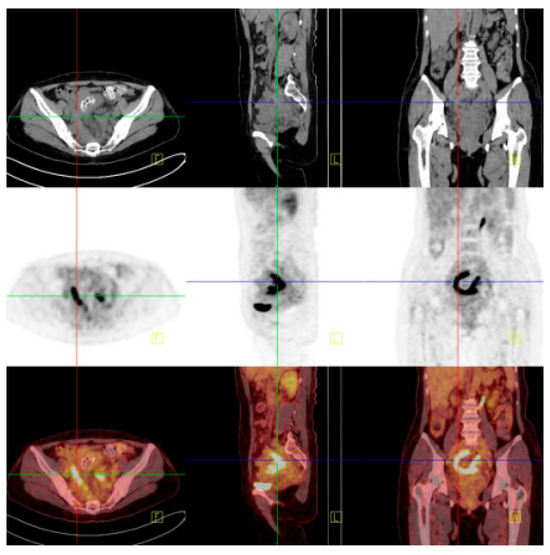

Figure 3. The preoperative ultrasound detection of pelvic mass: (A) ultrasound detection of a mass of about 8.8 × 4.4 × 4.8 cm in the right adnexa, with abundant blood flow signals, RI: 0.65. (B) The mass is not clearly demarcated from the rectum, sigmoid colon, and sacroiliac ligament. (C) Ultrasound shows thickening and decreased echo of the intestinal wall behind the uterus, with abundant blood flow. (D) Multiple enlarged lymph nodes in the bilateral iliac fossa. (E) A copper-bearing intrauterine contraceptive device, in the normal position. (F) The size and shape of the left ovary are acceptable.

Diagnostics 14 01923 g003